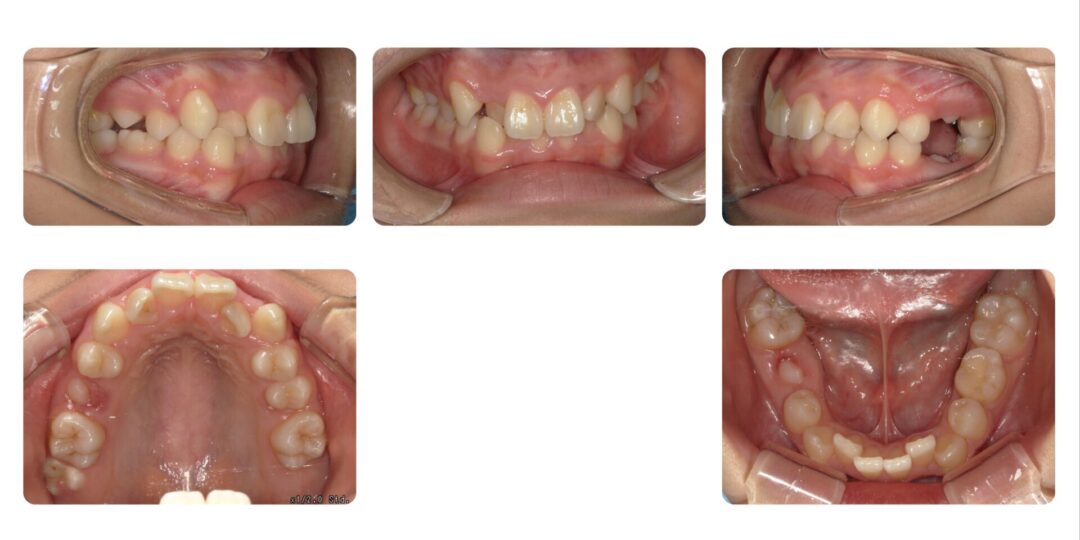

矯正治療前

右上3番目が気になる

初診時12歳

成人矯正 上顎左右第一小臼歯抜歯 マルチブラケット矯正

2年10ヶ月